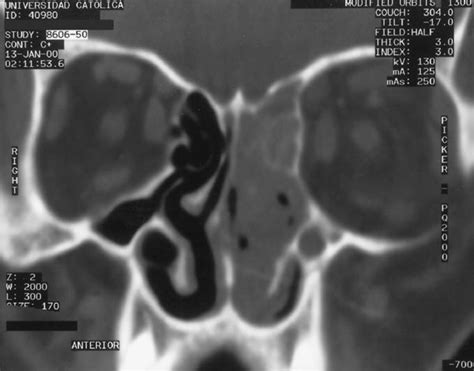

Mucormycosis is an opportunistic infection that typically develops in patients with weakened immune systems, diabetes, kidney failure, organ transplants, or chemotherapy for cancer. These molds live throughout the environment. It occurs in some people with a weakened immune system. These fungi are common environmental organisms that only cause disease when immunity is impaired. Early paranasal sinus involvement appeared as mucosal thickening on ct scans, usually without air/flui. Symptoms depend on the part of the body infected. Mucormycosis mucormycosis (previously called zygomycosis) is a serious but rare fungal infection caused by a group of molds called mucormycetes. Mucormycosis (zygomycosis) is a serious, potentially deadly fungal infection that's infrequently diagnosed.

Infections due to zygomycetes, caused by mucorales and entomophthorales, are characterized by angioinvasion and invasion of neighboring organs or structures. A greater understanding of the pathogenesis of the disease may lead to future therapies. Computed tomographic (ct) scans of ten patients with rhinocerebral mucormycosis were reviewed. Mucormicosis rinocerebral de origen dental reporte de caso clinico revision de la literatura. Early paranasal sinus involvement appeared as mucosal thickening on ct scans, usually without air/flui. Mucormycosis mainly affects people who have health problems or take medicines that lower the body's ability to fight germs and sickness. However, because zygomycota has been identified as polyphyletic, and is not included in modern fungal classification systems, the diseases that zygomycosis can refer to are better called by their specific names: Mucorales most commonly cause rhinocerebral, pulmonary, cutaneous or disseminated infection and its spread is favored by several diseases (suc … These molds live throughout the environment. It is a serious fungal infection that affects the sinuses, brain, eyes, lungs and the skin. Introduction mucormycosis is manifested by a variety of different syndromes in humans, particularly in immunocompromised patients and those with diabetes mellitus 1 . Mucormycosis (after mucorales), phycomycosis (after phycomycetes) and. Mucormycosis is a fungal infection of the sinuses, brain, or lungs.